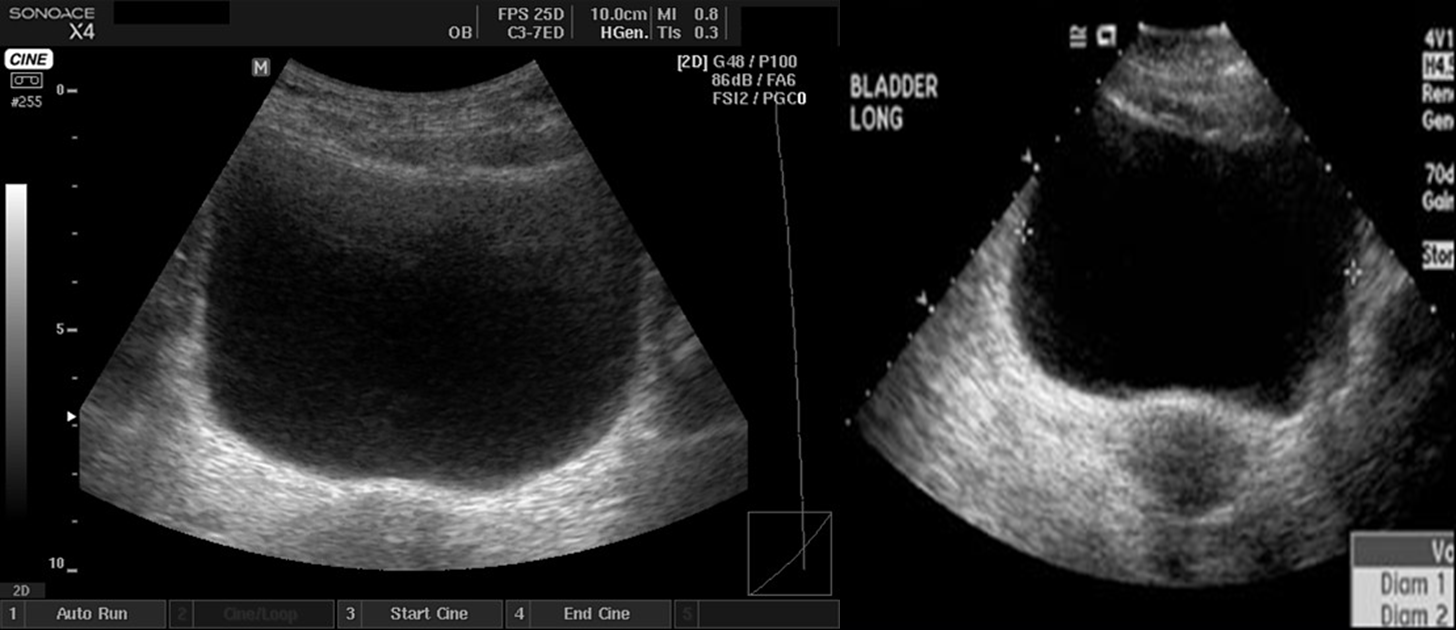

The urinary bladder should be examined in the distended state: the walls should be sharply defined and barely perceptible.

Male

Female